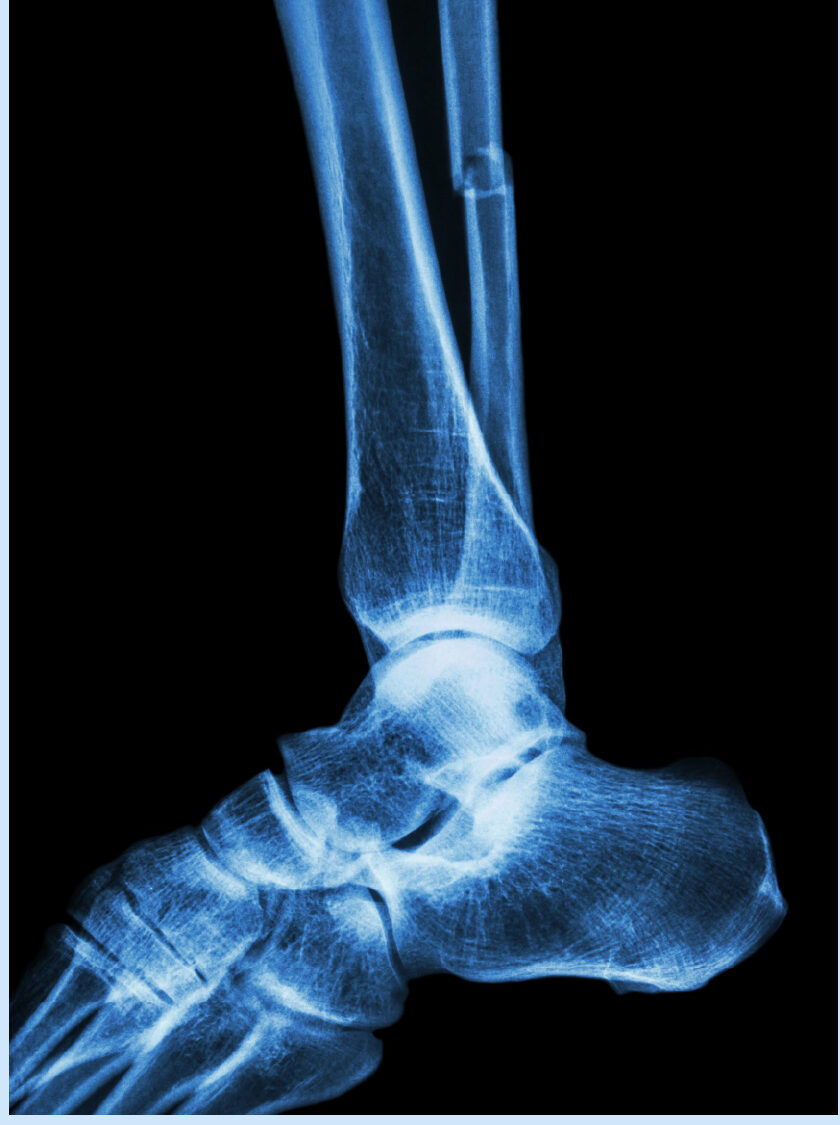

Ankle Injuries

• Ankle Fracture Fixation

• Syndesmosis Instability Fixation

• Achilles Tendon Rupture Repair

• Ankle Arthroscopy